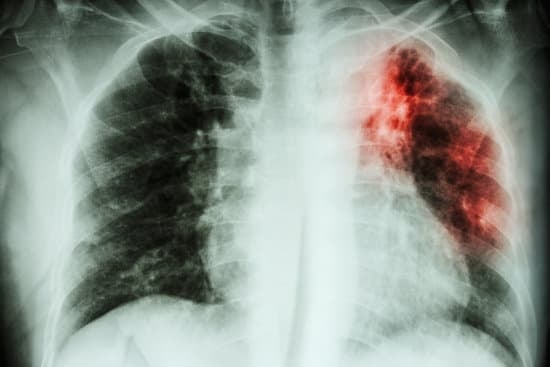

흉부 엑스레이

X-ray: 폐의 이상 여부를 확인합니다.